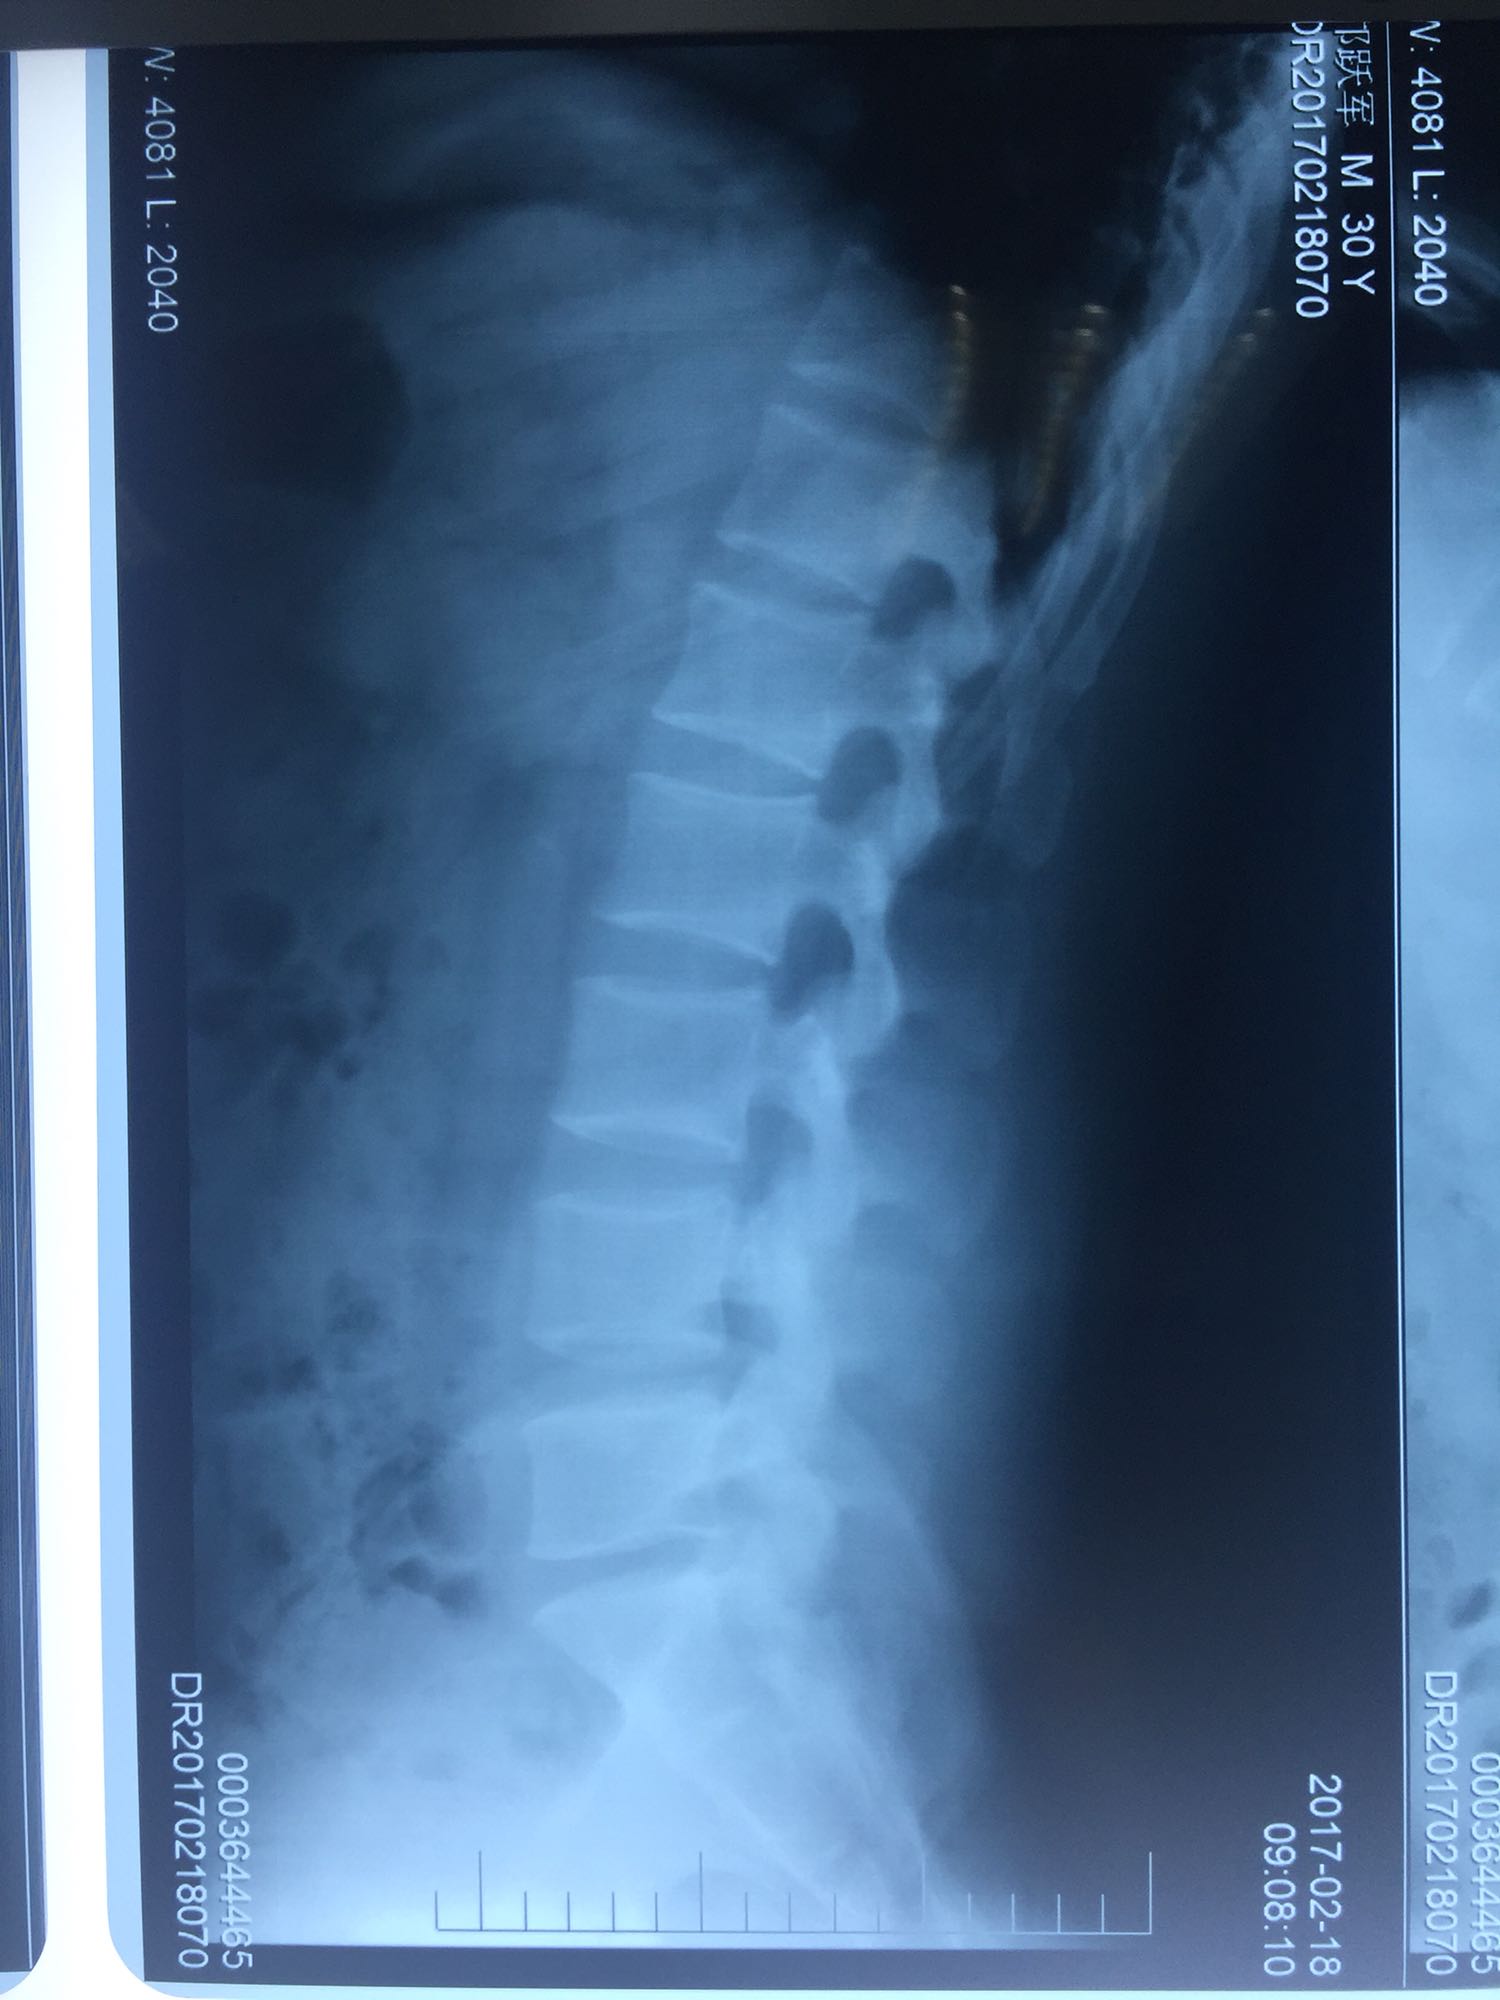

椎间孔镜下腰5骶1椎板间隙入路髓核摘除术

腰椎间盘脱出

邝X军,男性,30岁,因左下肢疼痛1天而入院。 1天前无明显诱因出现左下肢疼痛,程度较重,难以忍受,伴有行走困难。

腰骶部肌紧张,腰5骶1棘间及左侧椎旁有压痛及放散痛,左侧坐骨神经出孔处有压痛及放散痛,左侧足背外侧及足底部皮肤感觉麻木,左侧直腿抬高试验阳性(30度)。

诊断:腰5骶1椎间盘突出症 治疗方案:椎间孔镜下经椎板间入路髓核摘除术